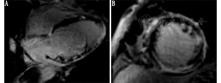

CMR延迟成像中的LGE可评估心肌瘢痕的情况(图2)。钆剂是一种细胞外显像剂,与正常心肌相比,其在纤维化或炎性反应心肌中的洗脱速率较慢。尽管LGE表现各异,结节病的病灶多位于室间隔、左心室基底部、侧壁及乳头肌,较少分布于心内膜下[39,42]。LGE的分布和整体表现有助于诊断CS,但其结果可能是非特异性的。LGE可以被定量,但目前定量诊断CS尚无共识。此外,CMR在安装心脏起搏器或植入式心律转复除颤器的患者中禁用,钆剂禁用于晚期肾病患者。